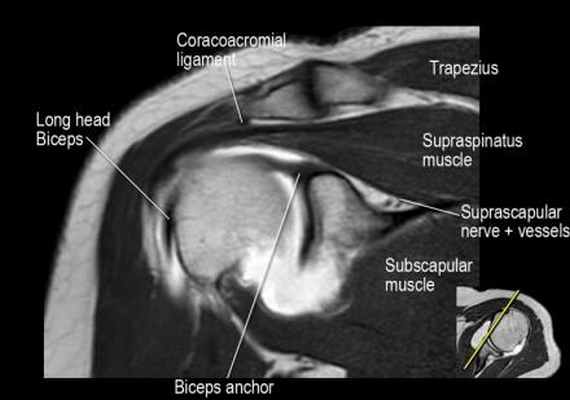

Нормальная корональная анатомия плечевого сустава и контрольный список

- обратите внимание на клюво-ключичную связку (coracoclavicular ligament) и короткую головку двуглавой мышцы (short head of the biceps).

- обратите внимание на клювоакромиальную связку (coracoacromial ligament).

- -

- обратите внимание на надлопаточный нерв и сосуды (suprascapular nerve and vessels)

- поищите импинджмент надостной мышцы за счет остеофитов в акромиально ключичном суставе или из-за утолщения клювовидноакромиальной связки.

- изучите верхний комплекс двуглавой мышцы и суставной губы, поищите подгубный карман илм SLAP-повреждение

- поищите скопление жидкости в подакромиальной сумке и повреждение сухожидия надостной мышцы

- поищите частичный разрыв сухожилия надостной мышцы в месте его прикрепления в виде кольцевидного повышения сигнала

- изучите область прикрепления нижней плече-лопаточной связки. Изучите нижний комплекс суставной губы и связок. Поищите HAGL-повреждение (humeral avulsion of the glenohumeral ligament).

- поищите повреждение сухожилия подостной мышцы

- обратите внимание на небольшое повреждение Хилл-Сакса